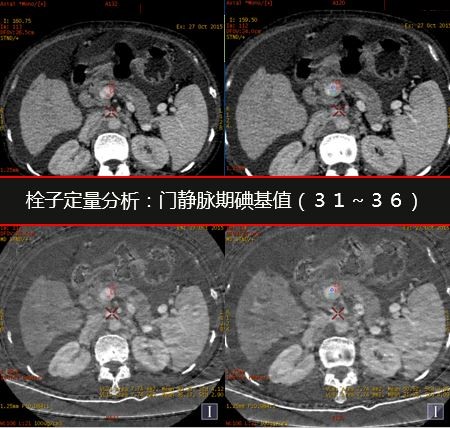

分别测量并计算正常肝脏及病灶在动脉期及门脉期的肝动脉碘分数(注1)及门脉碘含量(注2),结果见下表。

注: 1. 肝动脉碘分数AIF(Arterial Iodine Fraction)=碘含量(动脉期)/碘含量(门静脉期) 2. 门静脉碘含量PVIC(Portal Venous Iodine Concentration)=碘含量(门静脉期)- 碘含量(动脉期) 门静脉癌栓的显示: